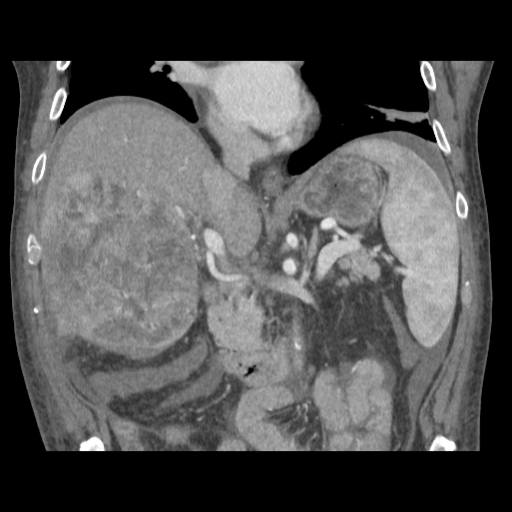

79 M with PMH of CKD, HLD, prostate cancer s/p prostatectomy + radiation presenting with feelings of fogginess, upset stomach, and diarrhea. Originally worked up at OSH, imaging concerning for a hepatic mass.

148/77 mmHg / 95 bpm / 15 breaths/min / 98.1°F / 98 ORA

sclera anicteric, no jaundice

AST 112, ALT 34, Alk Phos 202, CEA 2, CA 19-9 4